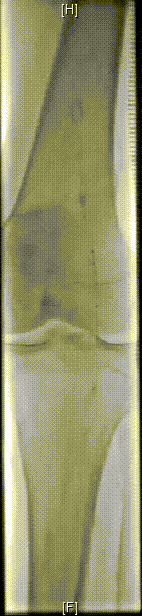

图为:股腘动脉DAART+区域性DES 最终造影

图为:2023年11月 2年后复查

2年后(2023-11)复查

下肢动脉CTA提示左股腘动脉通畅,DES区域未见内膜增生管腔丢失表现